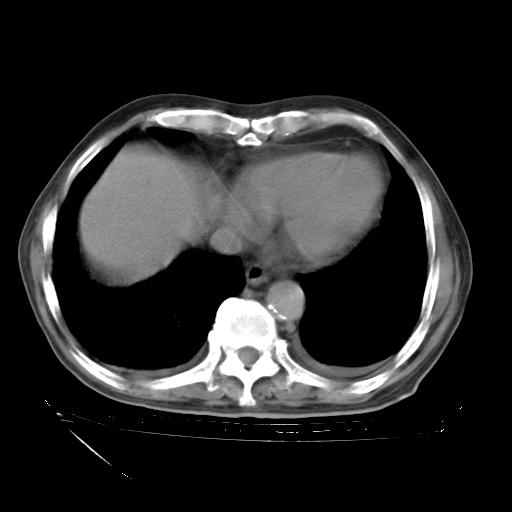

甲强龙80mg/日+抗结核治疗(异烟肼+利福霉素+乙胺丁醇)10天。复查肺部CT。

治疗10天肺部CT